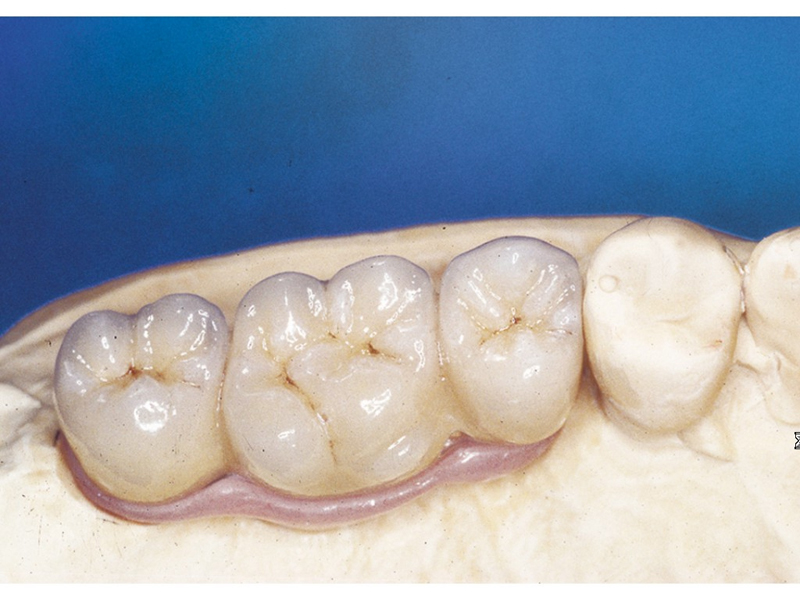

Náhrada jednoho zubu pomocí implantátu je možná také v postranním úseku chrupu. Při ztrátě většího počtu zubů ve frontálním nebo postranním úseku může být mezer uzavřena větším počtem jednotlivých implantátů.

Při ošetření pomocí jednotlivých implantátů zůstávají sousední zuby neporušené – intaktní. Při klasickém ošetření pomocí můstků musejí být tyto zuby obroušeny!

Protetické řešení může být pomocí můstku, který je kotvený na implantátech nebo pomocí jednotlivých korunek na implantátech.

V zásadě je možné do těchto můstků zařadit i přirozené zuby, zejména pokud je potřeba tyto zuby ošetřit proteticky

- korunkami. Korunky nebo můstky mohou být na implantáty nacementovány nebo přišroubovány.